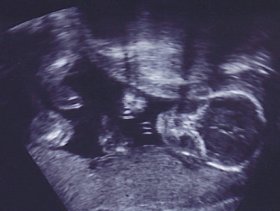

2) Υπερηχογράφημα Doppler: Είναι ένα υπερηχογράφημα Doppler αγγείων που μετράει τη ροή αίματος στον ομφάλιο λώρο για να διαπιστωθεί εάν ο πλακούντας τροφοδοτείται επαρκώς ή αν υπάρχουν σημάδια πλακουντιακής ανεπάρκειας και ενδομήτριας καθυστέρησης της ανάπτυξης.